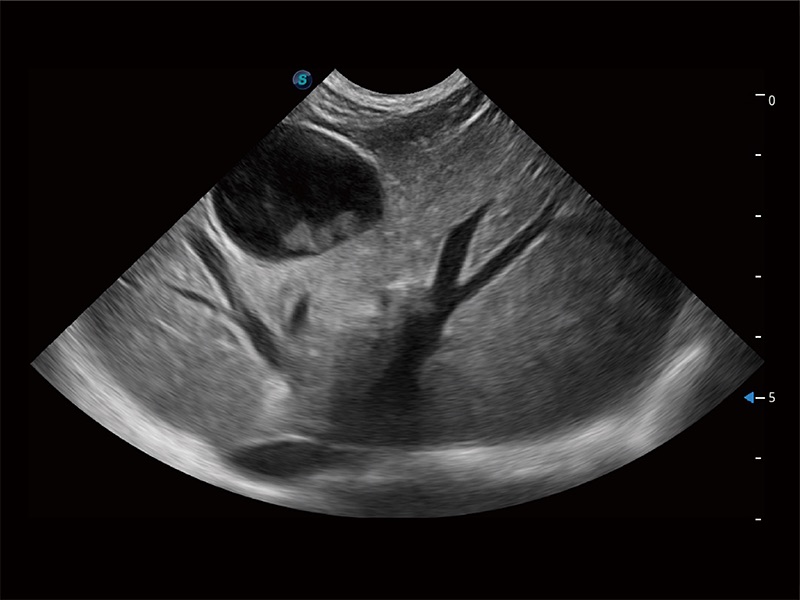

ProPet 80 专为动物医生设计,对不同的动物体型和生理结构作出了针对性的优化。通过动物影像专用软件,可满足个性化的应用需求,帮助动物医生获得更精确的诊断数据。

ProPet 80 全新的动物超声智能软件和丰富的探头群,为动物医生提供了高清晰度和精细分辨率的图像,无论在宠物、马科、畜牧还是实验室动物等应用中都可以轻松应对,为您的日常工作带来满意的体验。